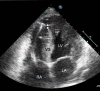

Echocardiographic guidance has an important role in percutaneous cardiovascular procedures and vascular access. The advantages include real time imaging, portability, and availability, which make it an effective imaging modality. This article will review the role of echocardiographic guidance for diagnostic and therapeutic percutaneous procedures, specifically, transvenous and transarterial access, pericardiocentesis, endomyocardial biopsy, transcatheter pulmonary valve replacement, pulmonary valve repair, transcatheter aortic valve implantation, and percutaneous mitral valve repair. We will address the ways in which echocardiographic guidance provides these procedures with detailed information on anatomy, adjacent structures, and intraprocedural instrument position, thus resulting in improvement in procedural efficacy, safety and patient outcomes.